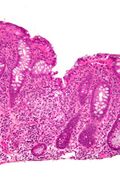

Additional images

Focal cryptitis and a granuloma. H&E stain.